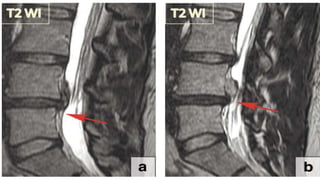

Extrusion Extrusion is thedisplacement of disc material with a full thickness disruption of the annulus fibrosus fibres Usually PLL remains intact

• 43.

Extrusion with sequestration •When extruded disc material that has no continuity with the disc of origin. • Fragment of disk may stay at the level of the disc or may migrate superiorly or inferiorly. • Pain and neurological symptoms may fluctuate with the migration of the free fragment within the spinal canal. • The acute displacement of a free fragment from the disc into the spinal canal may cause acute cauda equina syndrome